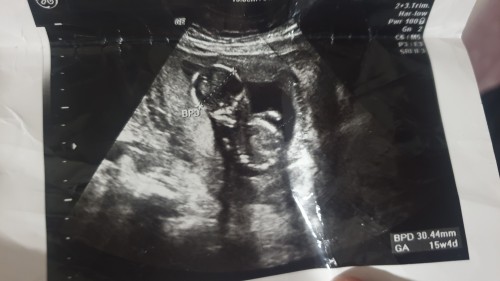

kizlar ikinci kez gittiim dr cinsiyetini gostermiyor ilk gittigimde ters duruyordu bu seferde bacagini kapatti bi turlu duzgun ultrasyon foto veremedi 16 haftaya giriyor sizin tahminleriniz varmi